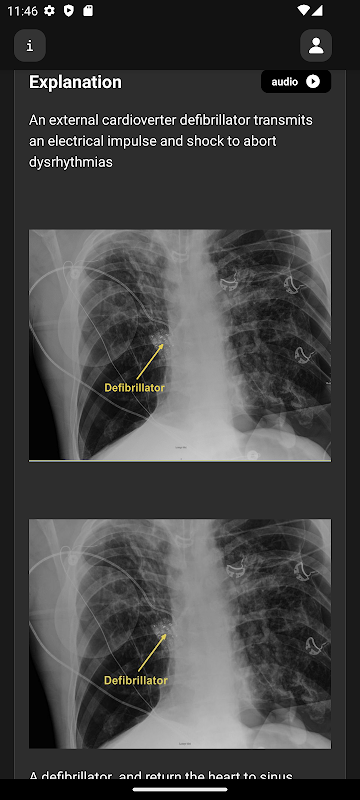

اعلی معیار کی ریڈیولاجیکل تصاویر، ویڈیوز اور متحرک تصاویر

ہر سوال کی تفصیلی وضاحت